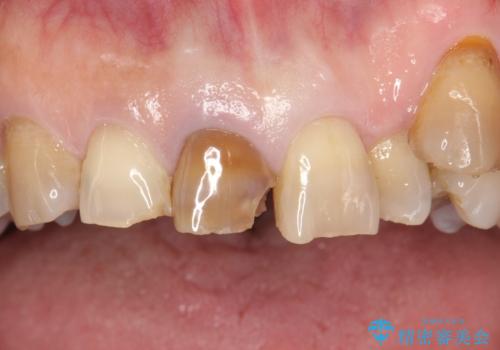

セラミックによる前歯の変色の改善

- 前歯の色が変色してきて、気になるとのことで来院されました。

オールセラミックを装着することで改善することとしました。